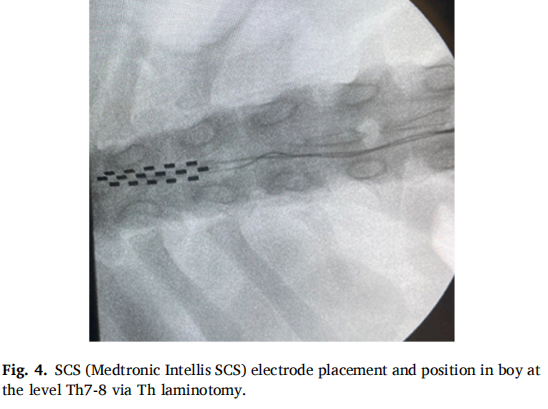

本研究采用 SCS硬膜外电极植入。病例1(CRPS1女性患者)接受下肢电极经皮植入T10水平,上肢电极通过右侧C6-C7椎间盘切除术放置;病例2(CIDP男性患者)通过T8椎板切开术在T7-8水平植入电极。两例均在全身麻醉下完成手术,避免使用神经肌肉阻滞剂以保留运动信号监测能力。植入后设置10天试验期评估疗效,确认有效后植入永久脉冲发生器。术中采用透视引导确保精准定位,术后定期调整刺激参数以优化治疗效果。病例2因脑脊液泄漏经历三次电极位置调整,最终更换为椎板切开术植入新电极。 图5